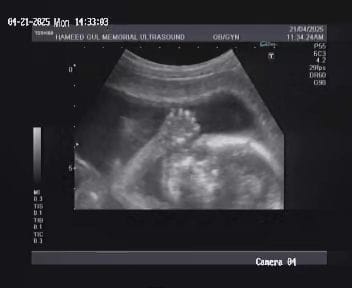

Ultrasound images

Our institutue provides high-quality ultrasound imagies for various diagnostic applications. these images serve as essential tools for accurate diagnostic and treatment planning.